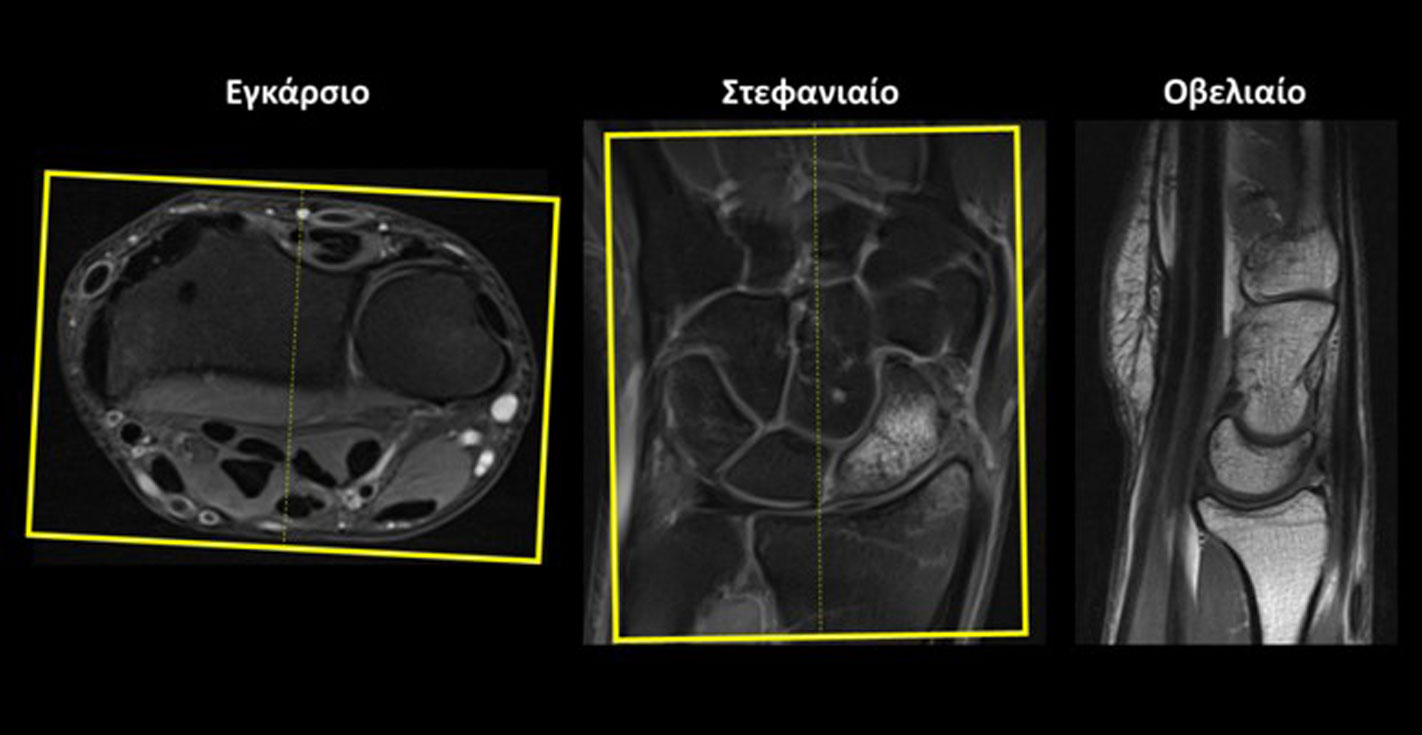

Στεφανιαίο (Coronal): οι στεφανιαίες τομές σχεδιάζονται παράλληλα με τη νοητή γραμμή που ενώνει τη στυλοειδή απόφυση της κερκίδας και της ωλένης στο εγκάρσιο επίπεδο και κάθετα στην ΠΧΚ άρθρωση στο οβελιαίο επίπεδο. Οι τομές πρέπει να περιλαμβάνουν ολόκληρη την ΠΧΚ άρθρωση από μπροστά έως πίσω.

Εγκάρσιο (Axial/Transversal): οι εγκάρσιες τομές σχεδιάζονται παράλληλα με τη ΠXΚ άρθρωση τόσο στο στεφανιαίο όσο και στο οβελιαίο επίπεδο. Οι τομές πρέπει να περιλαμβάνουν ολόκληρη την ΠΧΚ άρθρωση από πάνω έως κάτω.

Οβελιαίο (Sagittal):οι οβελιαίες τομές σχεδιάζονται κάθετα στη νοητή γραμμή που ενώνει τη στυλοειδή απόφυση της κερκίδας και της ωλένης στο εγκάρσιο επίπεδο και κάθετα στην ΠΧΚ άρθρωση στο στεφανιαίο επίπεδο. Οι τομές πρέπει να περιλαμβάνουν όλα τα οστά του καρπού από έσω προς τα μέσα.